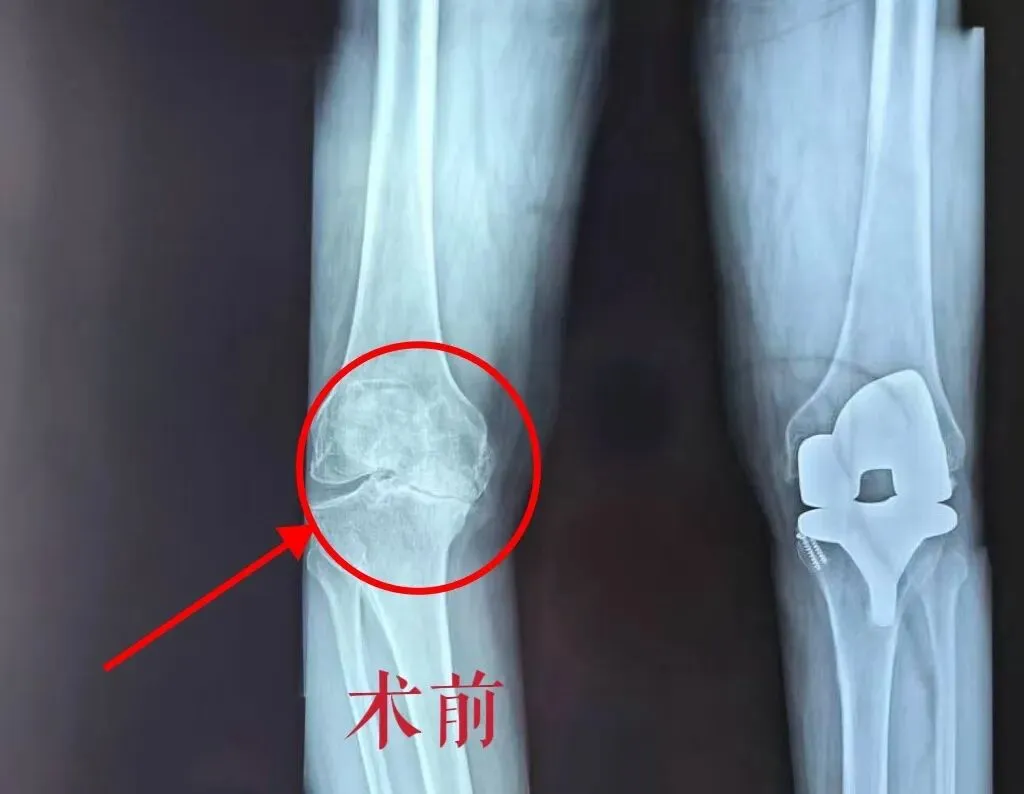

术前问题/ 骨科

• ✗ 关节间隙磨没了(骨头磨骨头)

• ✗ 腿弯成O型(内翻15°)

• ✗ 只能弯75°,连上厕所都蹲不下

• 研磨征(+):骨头磨骨头,像两块石头互相摩擦

诊断:重度右膝骨性关节炎(已到晚期,保守治疗无效)

术前后对比

术前术后对比/ 骨科

术前     术后